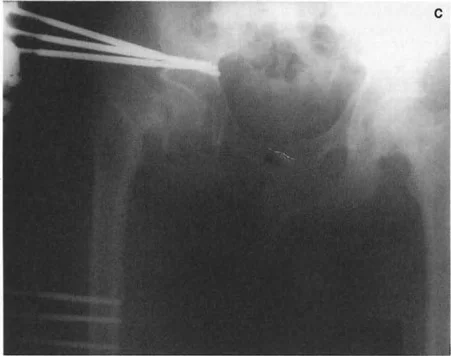

التدخل الجراحي: قطع العظم (Osteotomy)

عندما تفشل العلاجات التحفظية في تخفيف الأعراض أو عندما يكون التشوه شديدًا ويُهدد وظيفة المفصل على المدى الطويل، يُصبح التدخل الجراحي ضروريًا. تُعد عملية قطع العظم (Osteotomy) إجراءً جراحيًا يتم فيه قطع العظم وإعادة تشكيله لتصحيح التشوه وإعادة محاذاة المفصل. يُطبق الأستاذ الدكتور محمد هطيف مبادئ بالي (Paley's Principles) بدقة متناهية لضمان تصحيح مثالي وتجنب المضاعفات.

تنفيذ قطع العظم في المستوى السهمي

تُعالج التشوهات العظمية المصحوبة بأعراض في الجزء القريب من عظم الفخذ والتي تفشل في الاستجابة للعلاج التحفظي عن طريق قطع العظم التصحيحي. يجب أن تتبع عمليات قطع العظم هذه بشكل صارم قواعد بالي لتصحيح التشوهات الزاوية لتجنب إحداث انحرافات ميكانيكية المنشأ.

في الجزء القريب من عظم الفخذ، غالبًا ما يقع CORA لتشوه سهمي في الجزء العلوي من عنق الفخذ أو حتى داخل رأس الفخذ. ومع ذلك، لأسباب تتعلق بالشفاء البيولوجي وتثبيت الأجهزة، غالبًا ما يتم إجراء قطع العظم في مستوى أدنى بكثير، عادة في منطقة ما بين المدورين أو تحت المدور.